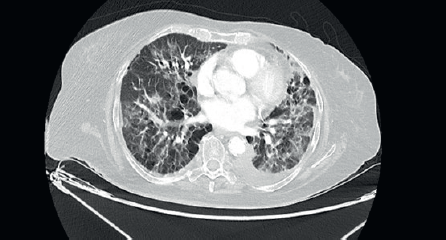

She was started on 3-monthly Zoledronic acid and palbociclib with Letrozole. There was significant reduction in size of the breast lesion, with healing of the breast ulcer and clinical improvement in terms of her bone pains. Four months later, she developed dry nonproductive cough and worsening breathlessness on exertion with no history of fever or prodromal illness. She was non-neutropenic with no renal or hepatic dysfunction. Arterial blood gas showed hypoxaemia and type 1 respiratory failure. Her high-resolution computed tomography (CT) thorax (Figure 2) was compared with her baseline imaging (Figure 1) and showed multiple new patchy and confluent ground glass opacities (GGOs) in bilateral lung fields, suggestive of acute interstitial lung disease (ILD).

Figure 2. High-resolution CT thorax of the patient, taken at timepoint of clinical deterioration, three months after initiation of CDK 4/6 inhibitor (Palbociclib) therapy.